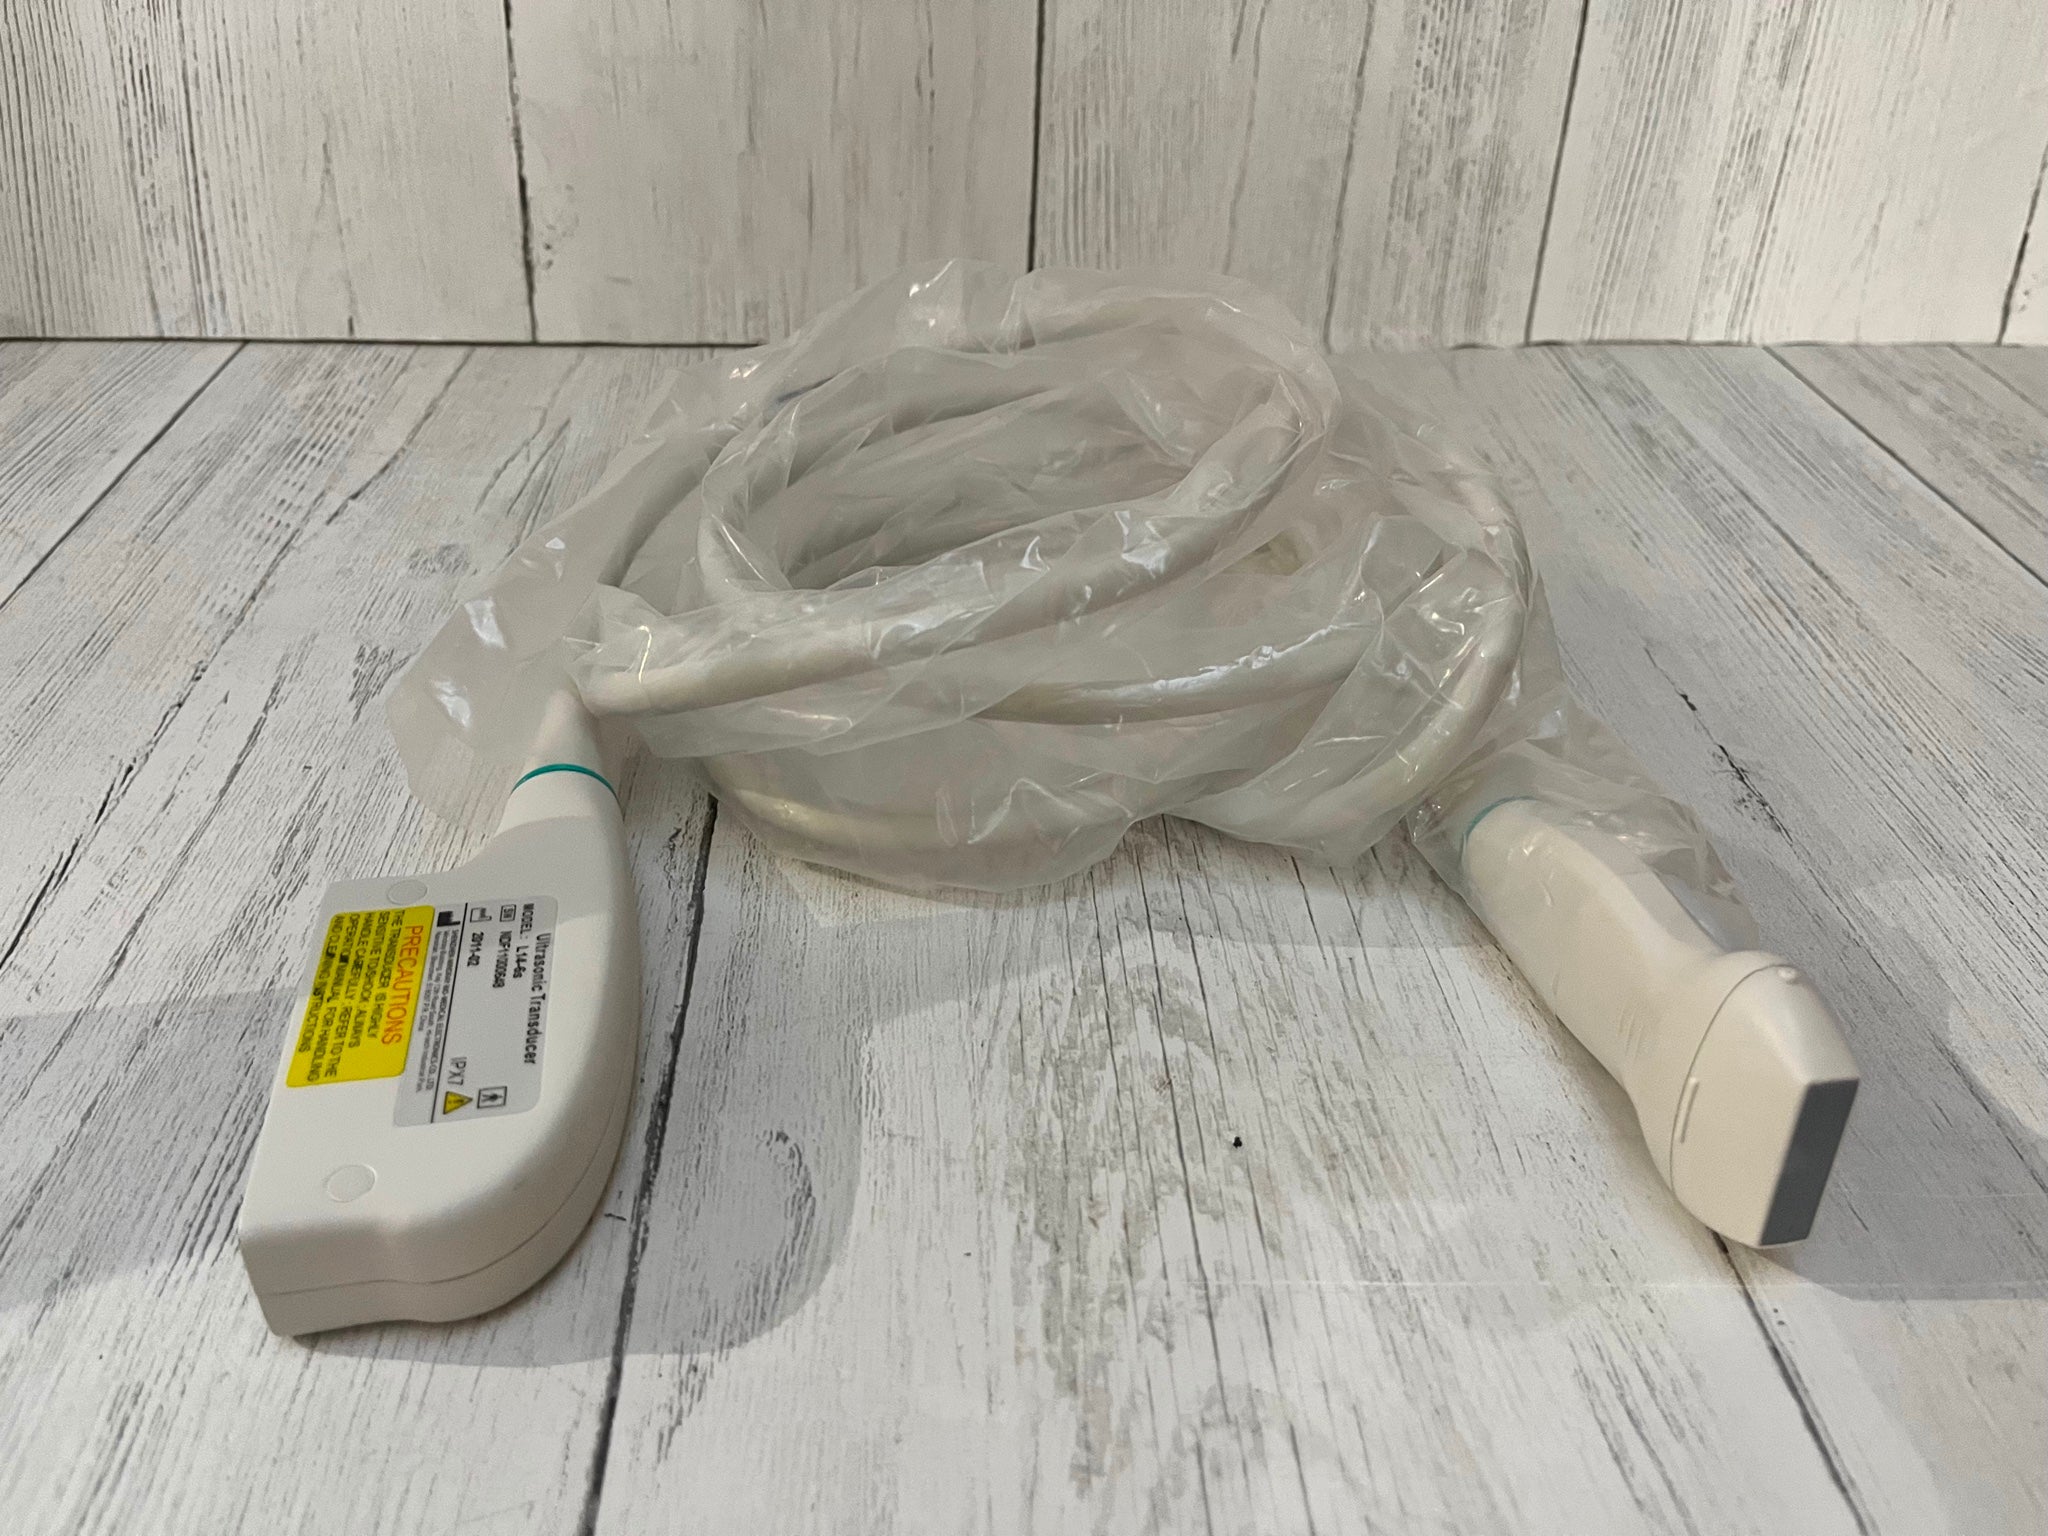

Pro Digital Laptop Ultrasound Machine Linear Array Probe + Transvaginal Probe

The included linear array probe provides high-resolution imaging, ideal for musculoskeletal, vascular, and soft tissue imaging. It delivers clear, detailed images for accurate diagnostics in various applications. The transvaginal probe is designed for internal imaging, offering clear visualization of the female reproductive organs, making it ideal for gynecological exams such as early pregnancy assessments and pelvic evaluations.